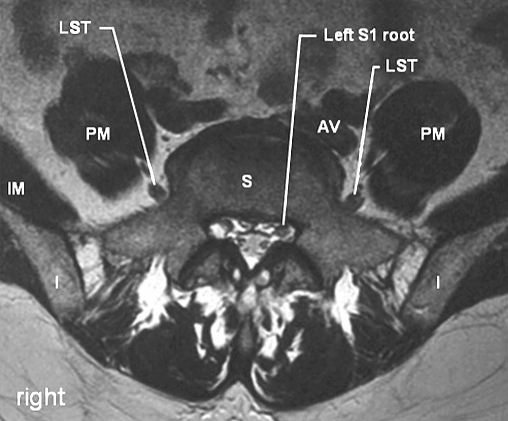

The first three and most of the fourth lumbar ventral rami descend laterally into the psoas major muscle and form the lumbar plexus [127, 171]. The smaller moiety of the fourth joins the fifth as the lumbosacral trunk that appears at the medial margin of the psoas major, descending over the pelvic brim anterior to the sacroiliac joint to join the first three sacral rami and part of S4 forming the sacral plexus (Fig. 1).

Fig.1 T2-.

weighted axial MRI at S1 level. AV arterio-venous bundle, I ilium, IM iliacus muscle, LST lumbosacral trunk, PM psoas major muscle, S sacrum